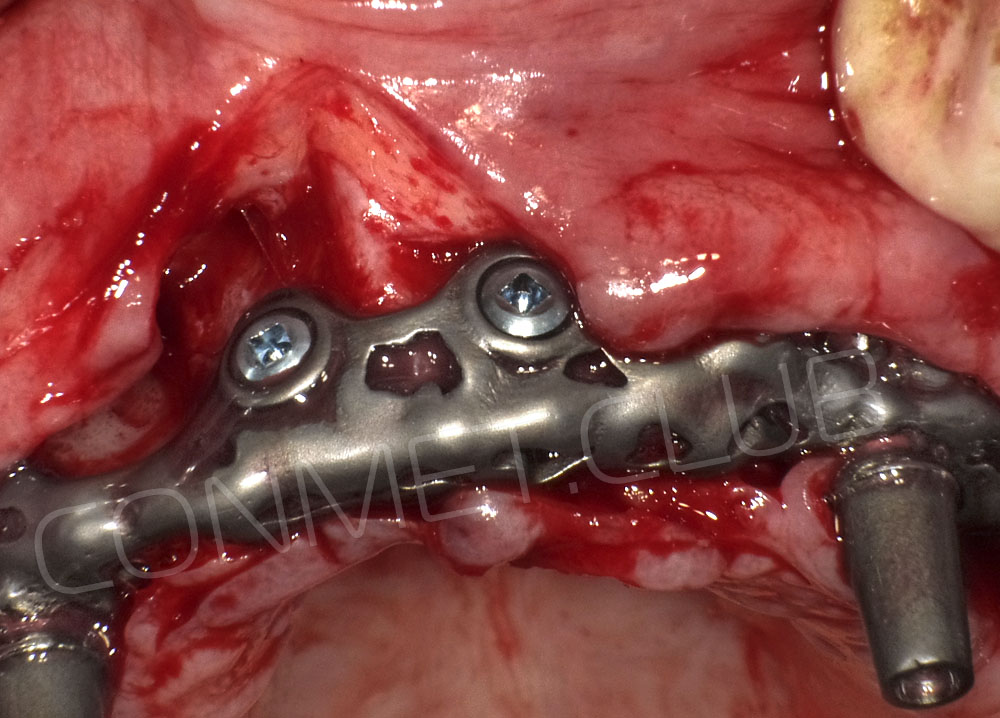

Сама же операция длиться 20-50 минут в зависимости от количества утраченных зубов. В процессе этой операции, после проведенной местной анестезии, делается разрез на слизистой, она приподнимается и субпериостальный имплантат укладывается на кость. После этого рана фиксируется несколькими швами и все! Через 10-14 дней мягкие ткани срастаются и надкостница надежно удерживает имплантат на месте. Нет необходимости ждать несколько месяцев, как это бывает в случае с внутрикостными винтовыми имплантатами.

Новые, искусственные зубы фиксируются к этому имплантату стандартными, трансокклюзионными винтами на 1-14 день (в данном клиническом случае на 5 сутки) и по существу являются несъемными!